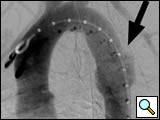

Figure 1: Left anterior oblique aortogram obtained with measuring pigtail catheter demonstrating aortic arch anatomy and location of aortic transection.

The patients are usually intubated as part of their initial resuscitation and have general anesthesia provided by an anesthesiology team for the procedure. In our institution, the procedure is performed in a conventional angiographic suite using ceiling-mounted Siemens Axiom ARTIS equipment (Erlangen, Germany). Patients are positioned supine with both groins prepped and draped. A 5-F graduated measuring pigtail catheter (Angiodynamics, Queensbury, NY) is inserted percutaneously via the left common femoral artery and a left anterior oblique arch aortogram is obtained to confirm arch anatomy and the location of the injury (Figure 1). Additional views, including selective vertebral artery injections, are performed as necessary.